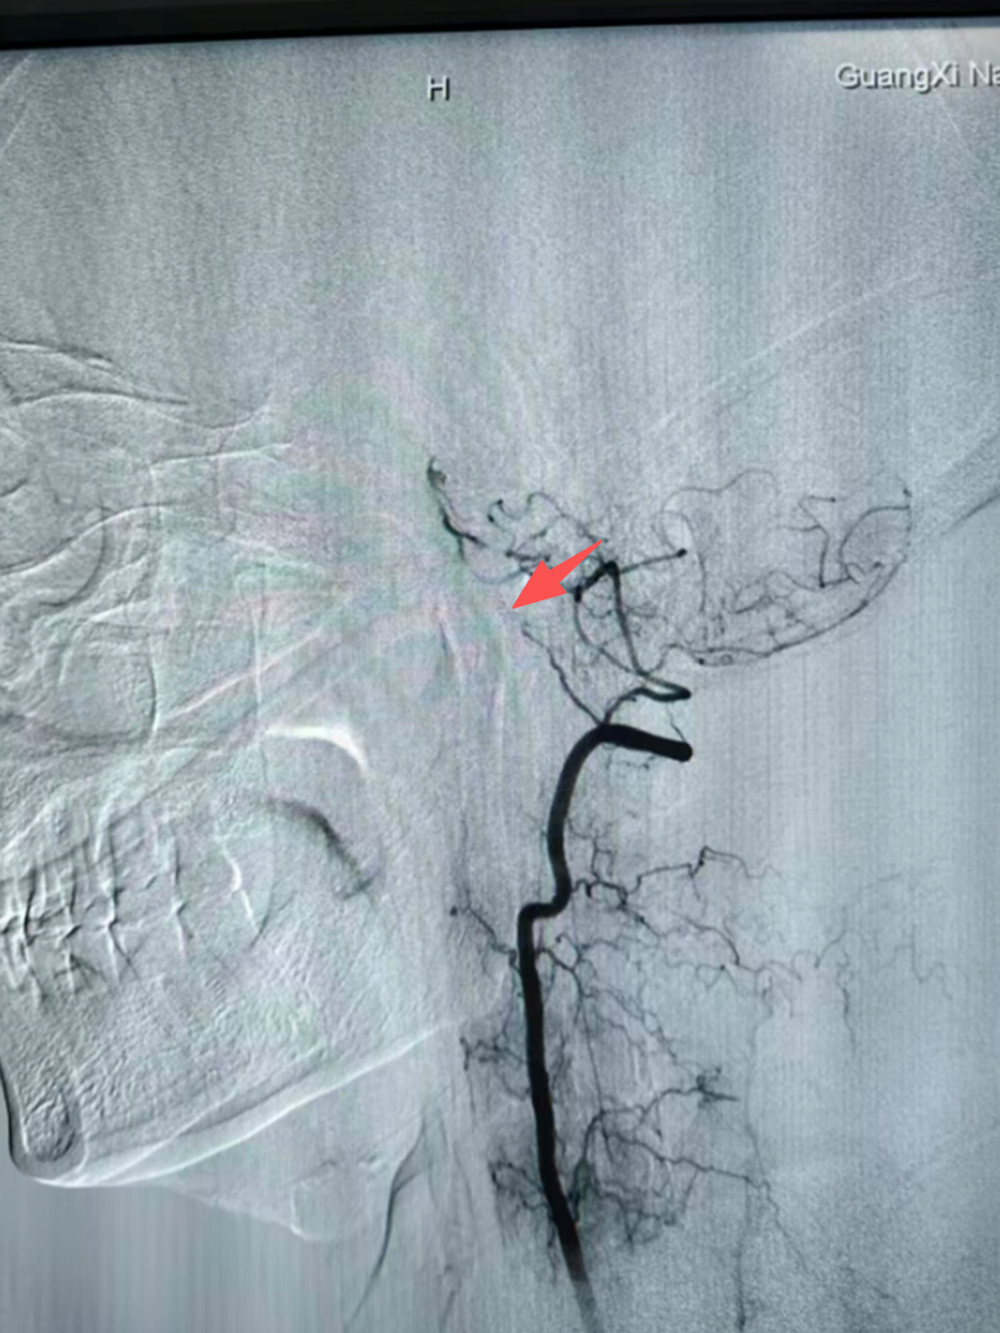

手术当天,气氛凝重。在DSA的引导下发现:患者右侧椎动脉发育不良,左侧椎动脉V4段呈长节段细丝样狭窄,基底动脉、大脑后动脉未显示。主刀乔振虎副主任手持一根细如发丝的微导丝,送入颅内球囊,开始了一场“毫米级”的跋涉,逐步扩张患者纤细的血管。血管路径异常迂曲,且伴有动脉粥样硬化斑块,这要求术者的操作必须兼具极高的精准性与极致的稳定性,每一步的导丝和球囊推进、每一次的“冒烟”造影确认位置,都是在为后续的血管再通铺平道路,同时要极力避免栓子逃逸、血管夹层或穿支动脉闭塞等严重并发症。

屏幕上,是错综复杂的血管网络。神经内科五区神经介入手术团队手中,是生命的全部重量,也是一个家庭的未来。时间在寂静中流淌,当那根承载着希望的微小球囊导管,在导丝的精准引导下,穿越迂曲的路径,终于抵达堵塞最严重的“隘口”时,手术进入了最关键阶段。

球囊被缓慢、精确地充盈,以恰到好处的压力扩张狭窄的血管壁。瞬间,屏幕上消失的血流信号重新开始跳跃、奔腾,如同枯竭的河床重新迎来了生命的溪流。“通了!”这一刻的静默,比任何掌声都更有分量。这不仅意味着一次血管内介入治疗的技术成功,更为一个家庭的期望,凿开了第一道切实的光芒。